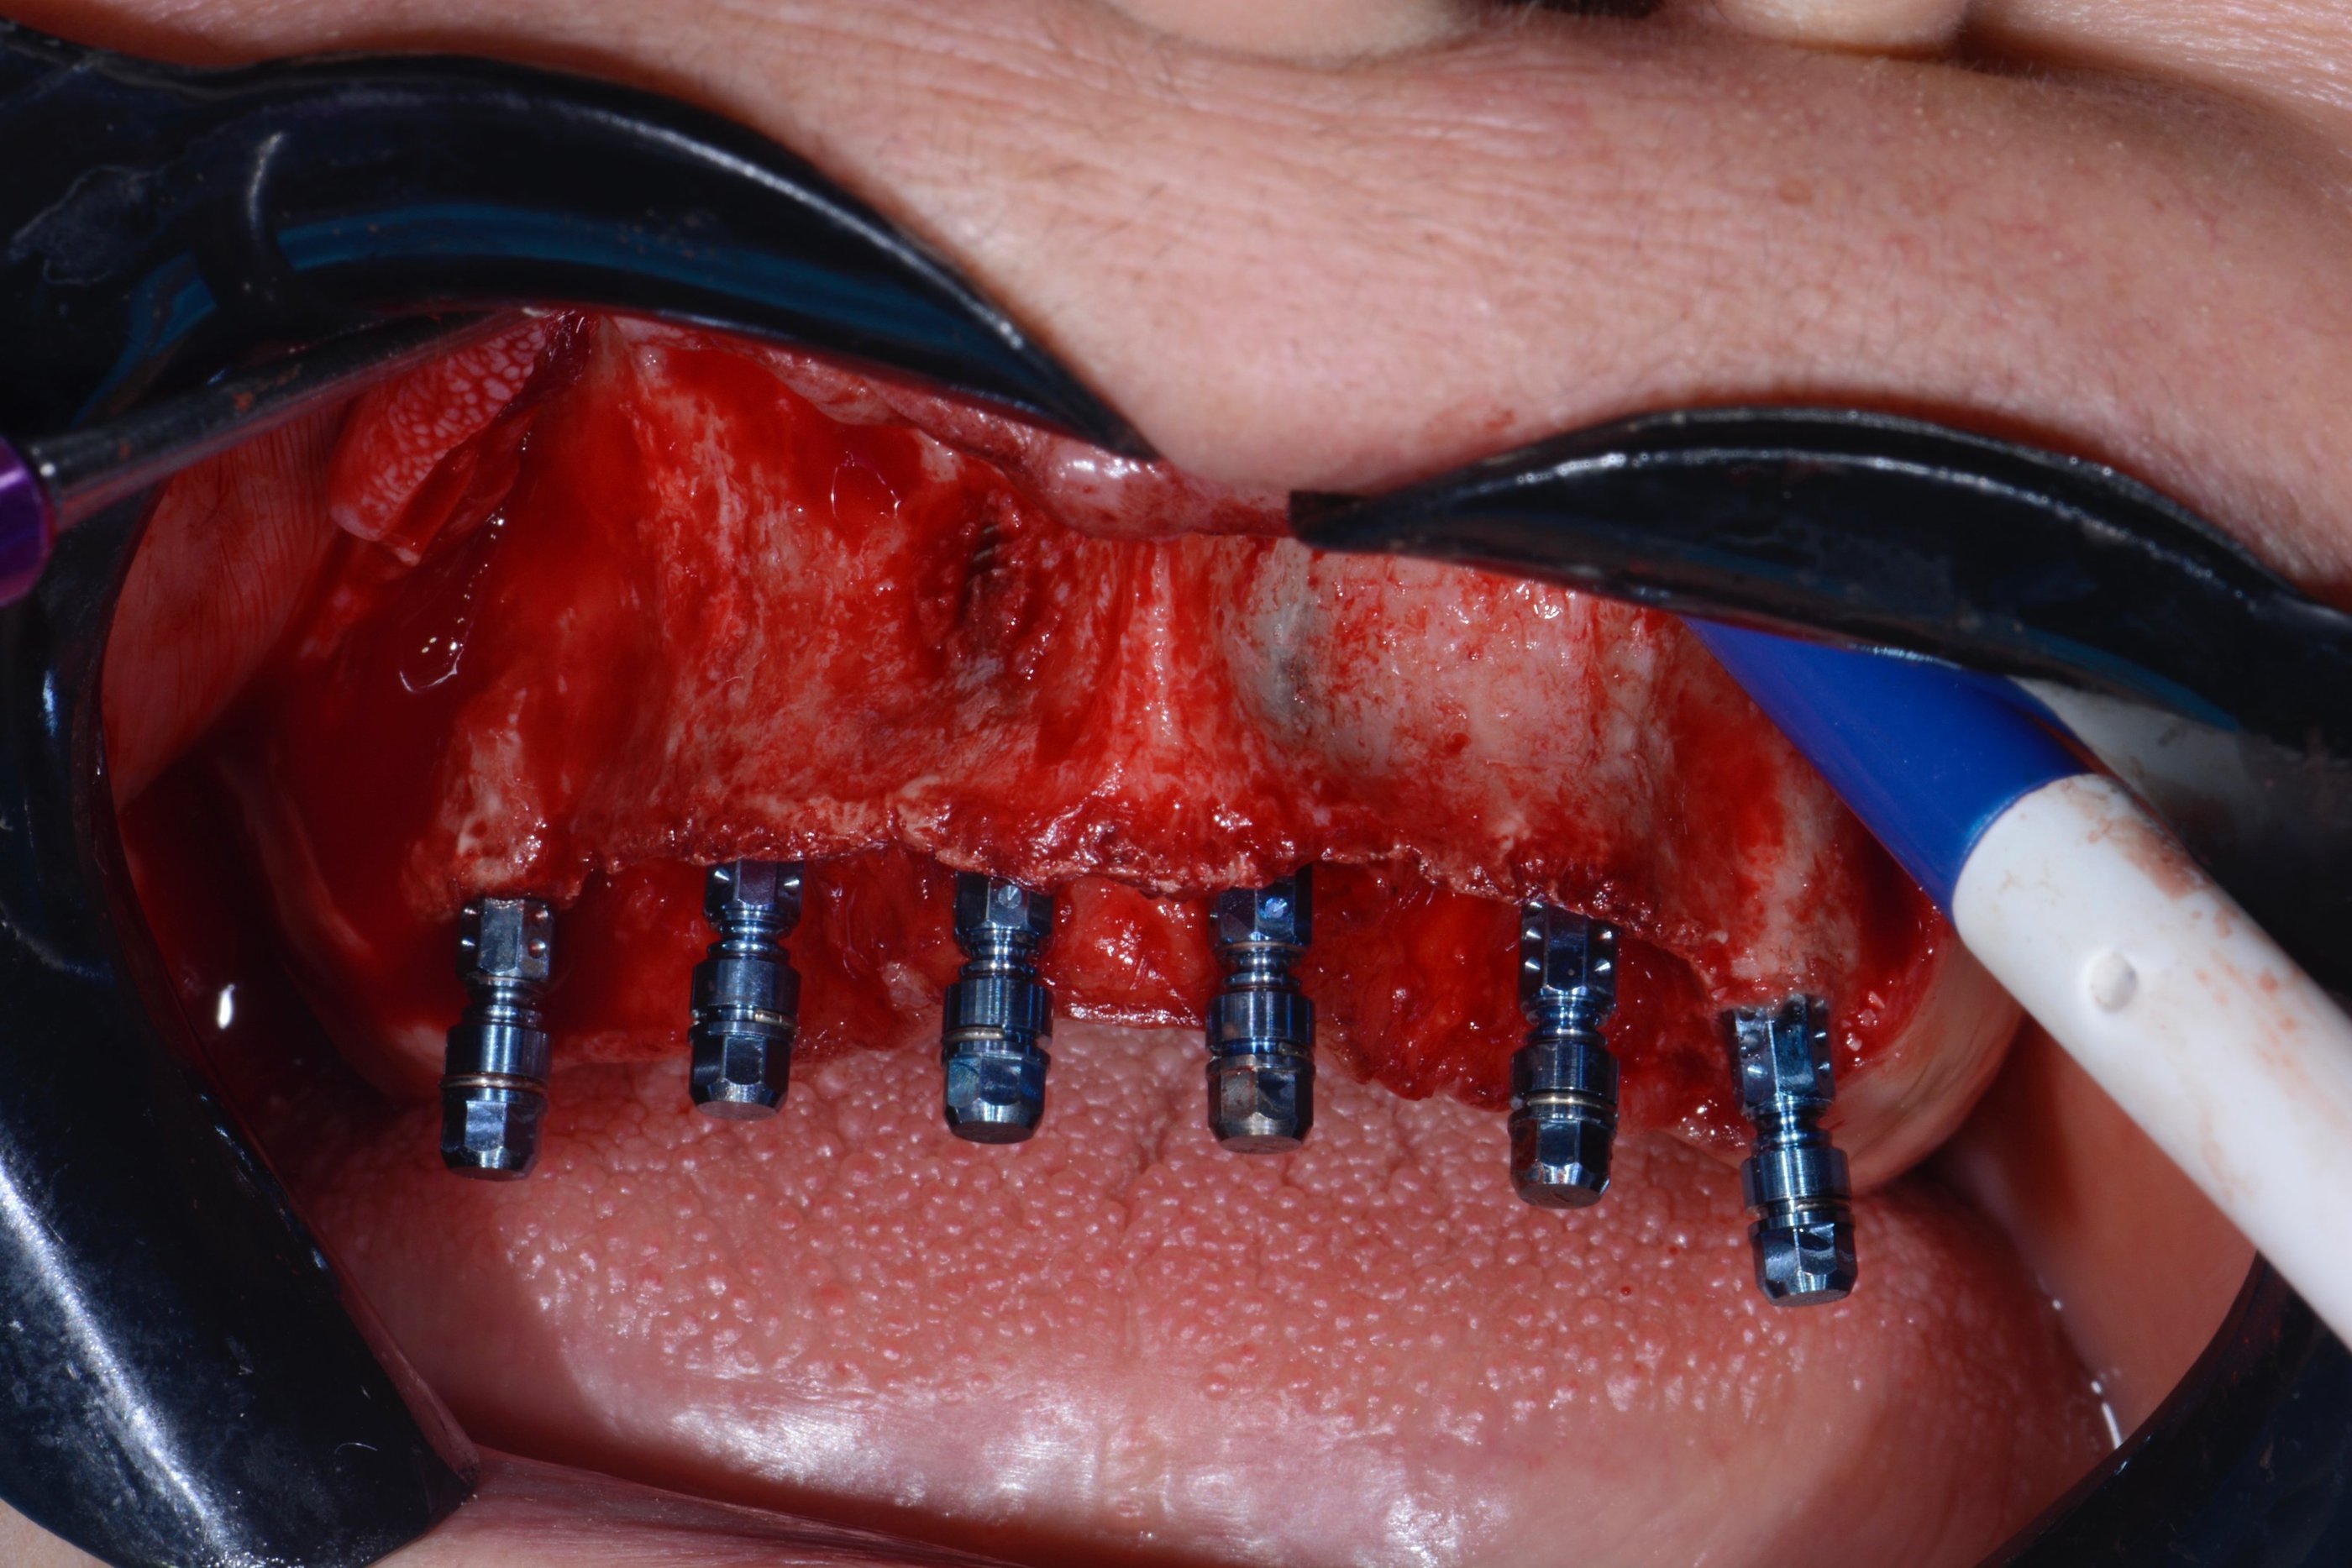

Curso especializado em técnicas de reabilitação com implantes dentários utilizando técnicas atualizadas e avançadas com planejamento digital em softwares específicos.

Treinamento prático para evolução nas técnicas de implantes.